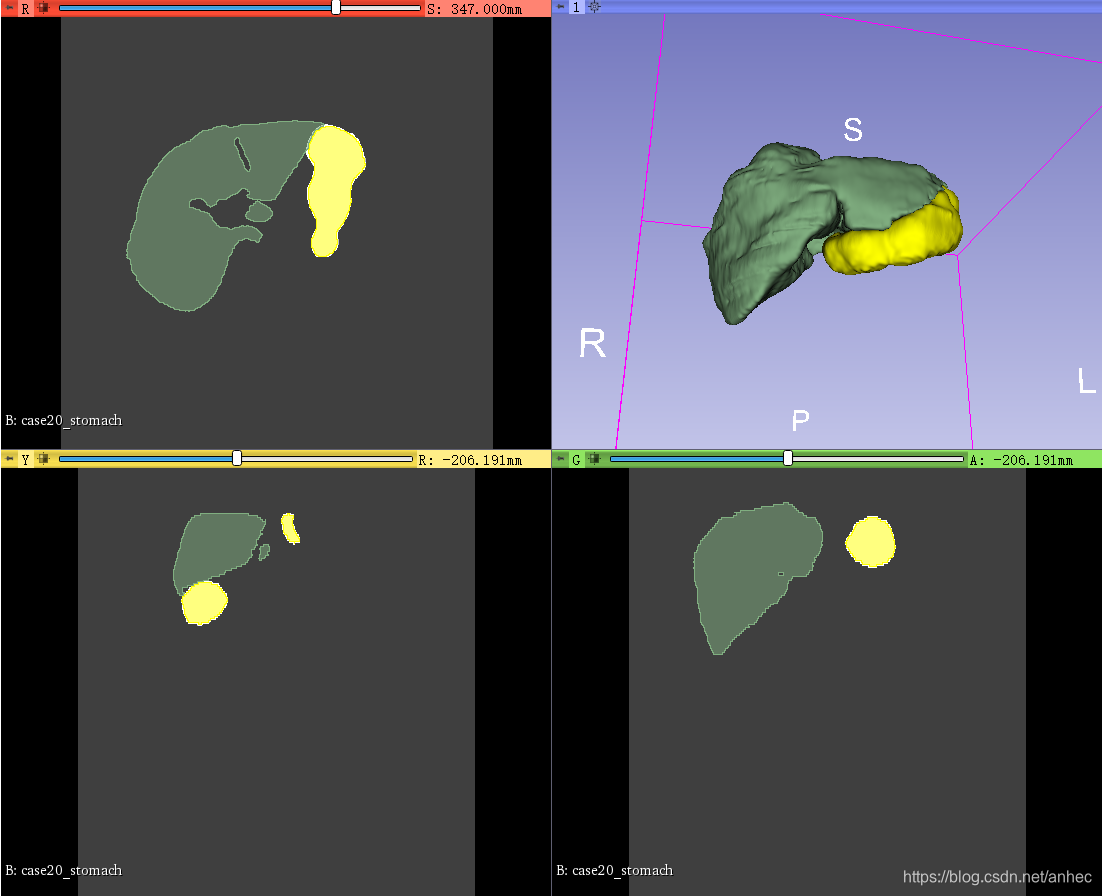

为每个label都添加Segment并apply之后,可以在右侧看到不同label的可视化图: